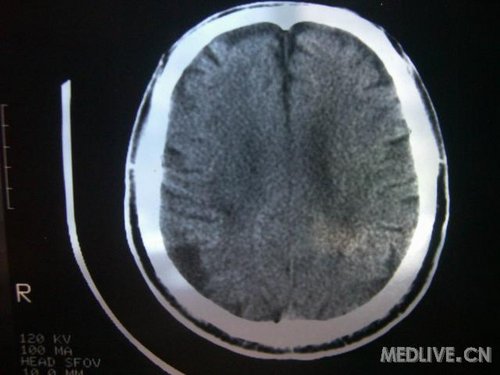

病人男性 73岁 市民 以“幻听、幻视两天,言语含糊、精神错乱一天”入院。

两天前无诱因出现幻听、幻视,描素眼前有彩色的圆圈,听见有人说话(但说什么不详),一天前出现胡言乱语,言语含糊,精神错乱,问话不答,行走略有不稳,来我院就诊,门诊头CT检查:(下面有片)入院后查体不合作,表情淡漠,问话不答,大致检查了一下,颅神经未见明显异常,颈软,右手活动似忽略差。其他检查不配合。脑电图:广泛轻-中度异常。

既往史:半年前曾患“右侧脑梗塞”但无明显后遗症,生活能自理,无高血压、糖尿病、心脏病史。

入院后,常规按脑梗塞治疗,病人不吃药,不输液,劝阻不住,有时打人,给于氯丙嗪25MG肌注,每日2次,症状有改善,近一两天,病人呈木僵状态,不说、不吃、不喝,液体可以进去。请各位战友分析一下:

此次入院时的片子: